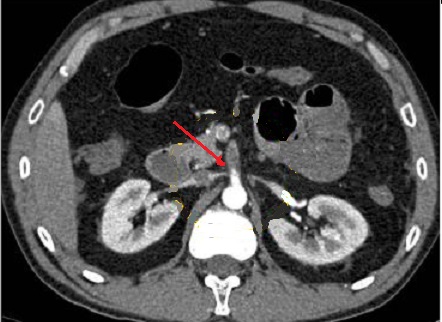

Même cas en coupe

axiale de TDM en phase arterielle . Fleche

rouge est image a íso-dense d'une thrombus de artere

mesenterique superieure . Aspect de fine de la paroi

de l'intestin se voyait encore sur cette coupe . |